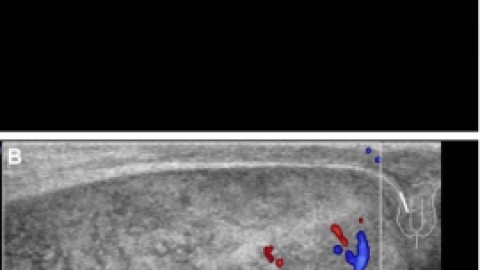

睾丸扭转的超声表现先天性解剖发育异常:精索过长、精索鞘膜附着异常形成“钟摆式”睾丸、睾丸引带缺如等。以下图片可能会让你不适,请谨慎↓↓↓此图来源网络另外睾丸扭转还分为:鞘膜外扭转和鞘膜内扭转,临床以鞘膜内扭转多见,多发生于婴幼儿及青少年。完全扭转:发作时,睾丸轻度肿大,实质呈不均匀低回声,精索扭曲成团,睾丸内无血流信号...